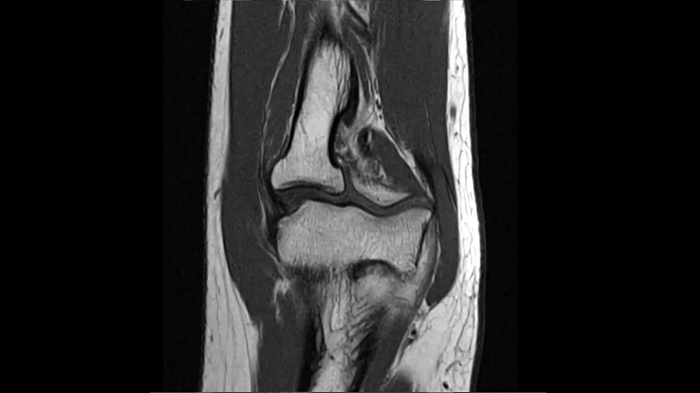

T1 SE

Outstanding T1 imaging of the knee using MAGNETOM Free.Star.

0.3 x 0.3 x 3.0 mm2

TA 2:54 minutes

MAC-ID: 7aaaa0198.

MAC-ID: 7aaaa0198. Image Credit: Siemens Healthineers